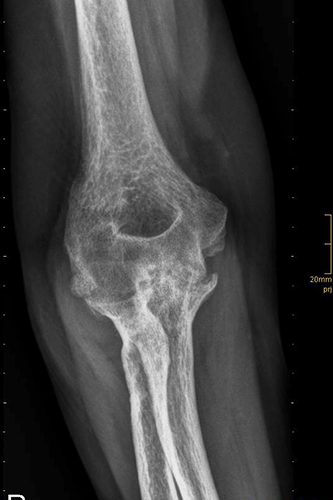

Vorher

Ellbogenröntgen seitlich

Cubitalarthrose Grad 4

Ellbogenröntgen ap